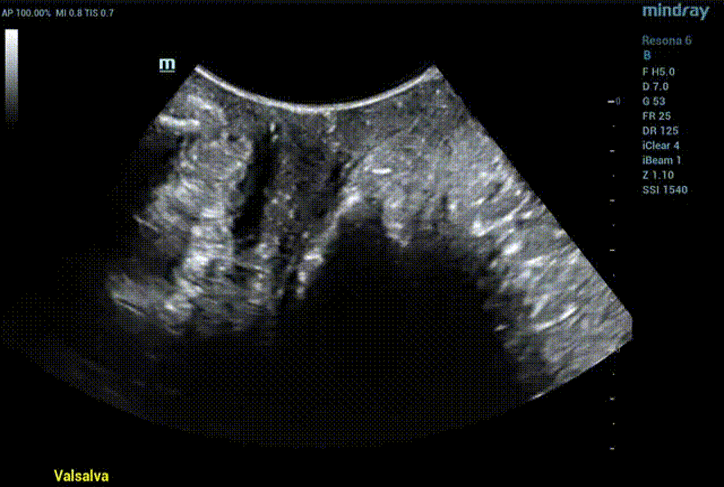

During maximal Valsalva maneuver, the bladder neck is 14mm below the pubic symphysis , the lowest point of bladder is 16.9mm below, the uterus is 7.3mm above and the rectum is 10.4mm below. The levator ani hiatus is 26.06cm2 (see Figure 2).

Figure 2 Two-dimensional ultrasonic measurement of pelvic floor structural parameters in Valsalva state